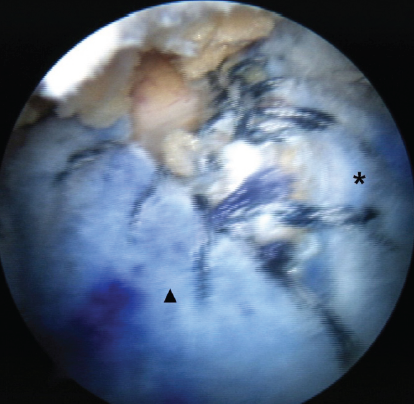

Figure 2: Intraoperative arthroscopy image of arthroscopy-assisted lower trapezius tendon transfer (aLTT) combined with superior capsular reconstruction (SCR) of the right shoulder. The SCR graft (asterisk) was attached to the supraspinatus footprint, and the interpositional graft (arrowhead) of aLTT was attached to the infraspinatus footprint. The interpositional graft was connected to the SCR graft with a side-to-side suturing technique.

In detailed surgical techniques, the lateral decubitus position and general anesthesia were used to prepare the patients. During the diagnostic examination with arthroscopy, the feasibility of repairing the supraspinatus and infraspinatus was assessed. The condition of the subscapularis and the long head of the biceps tendon was first assessed. Subsequently, SCR was carried out following the technique described by Mihata et al. A fascia lata autograft, including the intermuscular septum attached to the gluteus maximus, was harvested to ensure adequate thickness. The graft was folded 3–4 times to achieve a minimum thickness of 6 mm. The superior glenoid rim and the greater tuberosity footprint were decorticated to prepare for graft fixation. Two 4.5-mm PEEK Corkscrew anchors were inserted into the superior glenoid, and another two were placed at the supraspinatus footprint. The medial side of the graft was fixed using a mattress suture configuration, whereas the lateral aspect was secured with a double-row suture bridge technique, performed with the arm positioned in 30° of abduction (Fig. 1). The medial edge of the graft was secured using a mattress suture technique, while the lateral edge was affixed using the double-row suture bridge technique with lateral anchors in the shoulder at a 30° abduction position. After that, the LT tendon was harvested for aLTT. A skin incision approximately 5 cm in length was made along the scapular spine, extending from its medial border. The boundary between the LT tendon and the middle trapezius (MT) tendon was identified, and the LT tendon was separated from the MT tendon. A small incision was made in the infraspinatus fascia to provide a pathway for transferring the LT tendon. Then, the Achilles tendon allograft was folded 2 or 3 times to achieve a minimum thickness of 6 mm, a width of 2 cm, and a length of 15 cm, serving as an interpositional graft. One medial row anchor was inserted into the infraspinatus footprint. The interpositional graft was passed through the infraspinatus fascia into the subacromial space. After being placed on the infraspinatus footprint, the graft was fixed using medial-row and lateral-row anchors. The interpositional graft was connected to the SCR graft with a side-to-side suturing technique (Fig. 2).